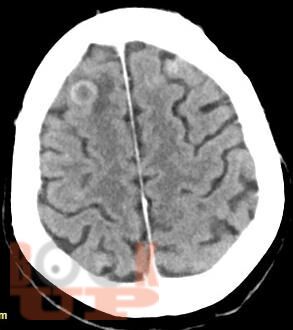

Учебное пособие освещает вопросы многоочагового поражения головного мозга. Рассматриваются различные нейрохирургические и неврологические заболевания с очагами поражения головного мозга в количестве более двух, такие как опухоли головного мозга (первичные и метастатические), воспалительные заболевания, демиелинизирующие заболевания, паразитарное поражение и другие патологии. В книге приведены алгоритмы дифференциальной диагностики данных заболеваний, начиная от особенностей клинической картины до специфики изменений сигнала в разных режимах МРТ. Также обозначена тактика ведения и прогноз заболеваний.